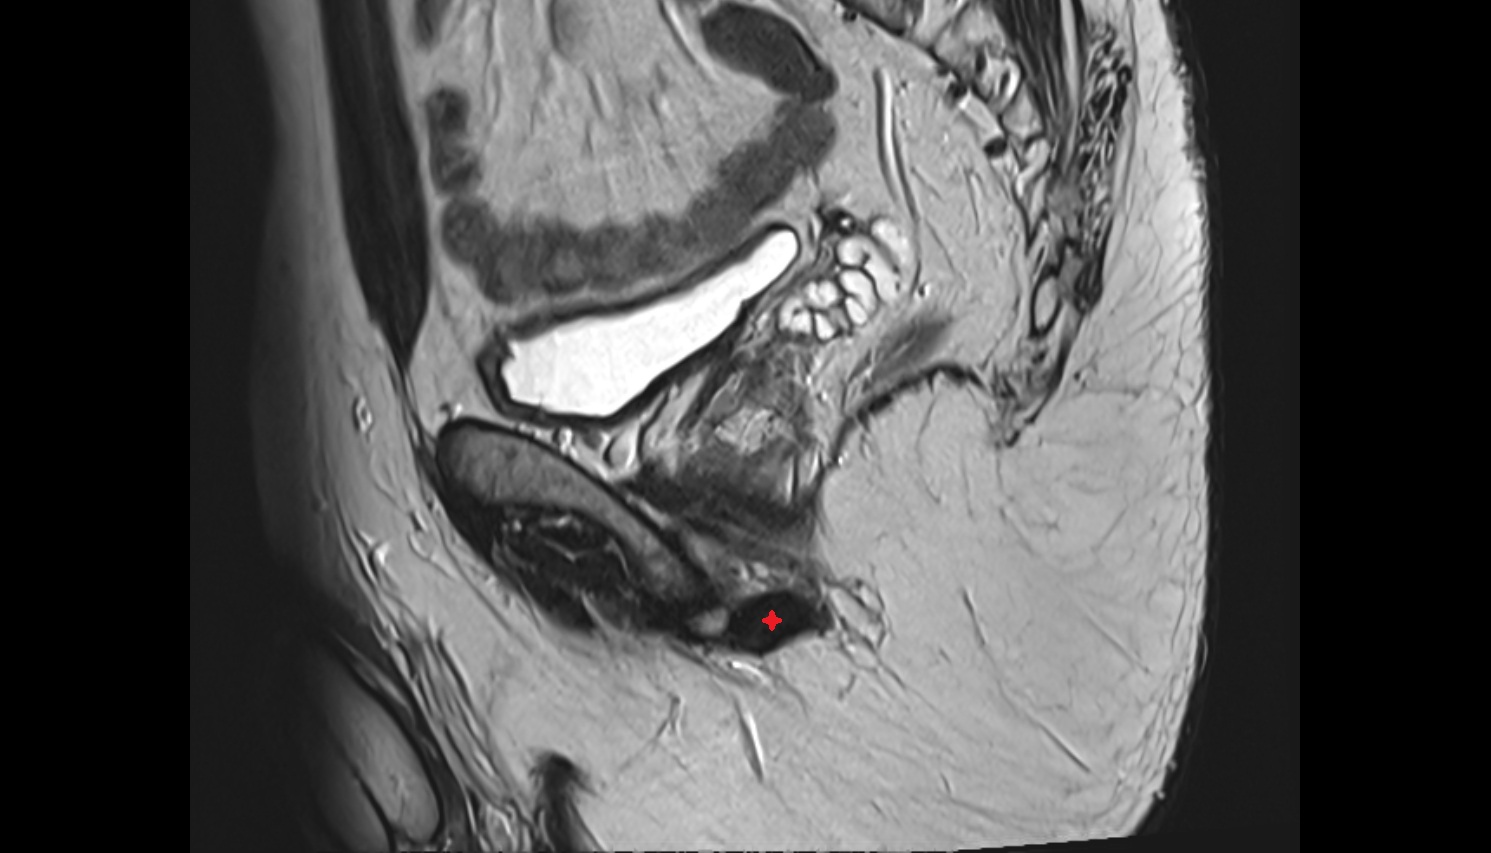

- Uterus

- Body of uterus

- Fundus of uterus

- Cervix of uterus

- Isthmus of uterus

- Vagina

- Fornix of the vagina

- Endometrium of uterus

- Myometrium of uterus

- Perimetrium of uterus

- Junctional zone of uterus

- Vesicouterine pouch

- Rectouterine pouch (pouch of Douglas)